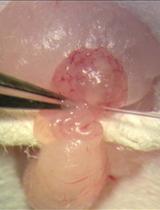

基于鸡胚绒毛尿囊膜的体内癌症转移模型

The Chick Embryo Chorioallantoic Membrane as an in vivo Model to Study Metastasis

Metastasis is a complex process that includes several steps: neoplastic progression, angiogenesis, cell migration and invasion, intravasation into nearby blood vessels, survival in the circulatory system, extravasation followed by homing into distant tissues, the formation of micrometastases, and finally the growth into macroscopic secondary tumors. This complexity makes metastases difficult to investigate and quantify in animal models. The chick embryo is a unique in vivo model that overcomes many limitations for studying the metastatic process, due to the accessibility of the chorioallantoic membrane (CAM), a well-vascularized extra-embryonic tissue located under the eggshell, that is receptive to the xenografting of mammalian tumor cells, including human. Since the chick embryo is naturally immunodeficient at this stage, the CAM can support the engraftment of tumor cells, and their growth therein can faithfully recapitulate most of the characteristics of the carcinogenic process including: growth, invasion, angiogenesis and colonization of distant tissues (Deryugina and Quigley, 2008; Zijlstra et al., 2002). The CAM sustains rapid tumor formation within 5-7 days after cancer cell grafting. This feature provides a unique experimental model for a rapid study of the intravasation and colonization steps of the metastatic cascade. Furthermore, using quantitative PCR to detect species-specific sequences, such as Alu, the chick embryo CAM model can be used to monitor and quantify the presence of the xenografted, ectopic tumor cells in distant tissues. Thus, the chick embryo model has proved a valuable tool for cancer research, in particular for the investigation of molecules and pathways involved in cancer metastasis and to analyze the response of metastatic cancer to potential therapies (Herrero et al., 2015; Casar et al., 2014). In this respect, the use of the rapid and quantitative spontaneous metastasis chick embryo model can provide an alternative approach to conventional mouse model systems for screening anti-cancer agents.